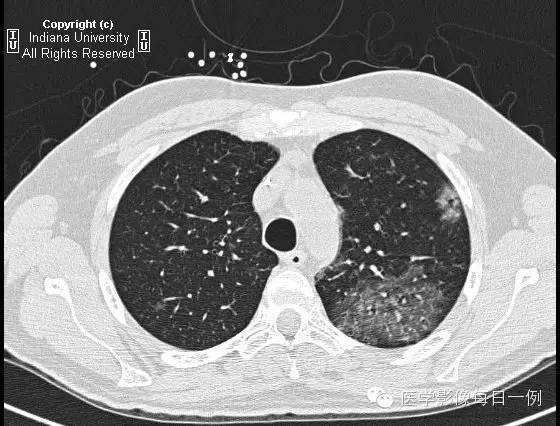

CT检查

【答案】2.D注释:支气管肺泡灌洗示肺出血,无合并性感染。

胸部CT示弥漫性肺泡透光度减低,主要位于右肺下叶和左肺上叶,呈铺路石样改变。胸膜无渗出。